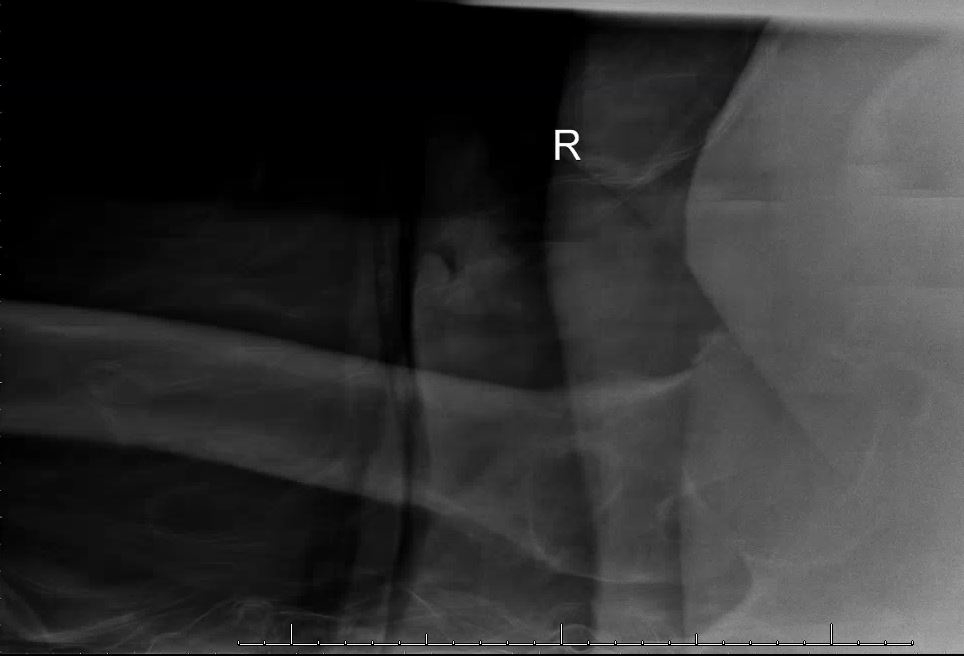

An x-ray of the hip showed a femoral neck fracture (Figures 1 & 2). The patient was taken to the operating room for emergent open reduction and internal fixation of the right femoral neck. During surgery the patient’s oxygen saturation decreased and he became hypotensive. Cardiopulmonary resuscitation was initiated but was ultimately unsuccessful.